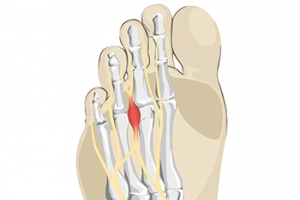

Constricting Shoes May Cause Morton’s Neuroma

Morton’s neuroma is one of the most painful foot conditions that can develop. The pain is felt between the third and fourth toes and results due to an inflamed nerve. If the arch is weak the nerve can become compressed, causing the tissues to thicken. This can happen from wearing shoes that do not have enough room for the toes to move freely in, therefore the nerve becomes irritated. A numbness or tingling sensation can often be felt with this condition and walking may become difficult. Morton’s neuroma may also gradually develop from extreme overpronation which is the foot continuously rolling inward while walking. This may cause the bones in the front of the foot to compress the nerve. Effective treatment generally begins with frequently resting the foot and some patients choose to insert a cushioned pad into the shoe. If you have developed Morton’s neuroma, please confer with a podiatrist who can effectively treat this condition while offering you pain relief options.

Morton’s neuroma is a very uncomfortable condition to live with. If you think you have Morton’s neuroma, contact one of our podiatrists of Brondon Foot and Ankle. Our doctors will attend to all of your foot care needs and answer any of your related questions.

Morton’s Neuroma

Morton's neuroma is a painful foot condition that commonly affects the areas between the second and third or third and fourth toe, although other areas of the foot are also susceptible. Morton’s neuroma is caused by an inflamed nerve in the foot that is being squeezed and aggravated by surrounding bones.

What Increases the Chances of Having Morton’s Neuroma?

- Ill-fitting high heels or shoes that add pressure to the toe or foot

- Jogging, running or any sport that involves constant impact to the foot

- Flat feet, bunions, and any other foot deformities

Morton’s neuroma is a very treatable condition. Orthotics and shoe inserts can often be used to alleviate the pain on the forefront of the feet. In more severe cases, corticosteroids can also be prescribed. In order to figure out the best treatment for your neuroma, it’s recommended to seek the care of a podiatrist who can diagnose your condition and provide different treatment options.

If you have any questions, please feel free to contact our office located in Centerville, OH . We offer the newest diagnostic and treatment technologies for all your foot care needs.

Morton's Neuroma

Morton's Neuroma, also called Intermetatarsal Neuroma or Plantar Neuroma, is a condition that affects the nerves of the feet, usually the area between the third and fourth toe. Neuroma refers to a benign growth that can occur in different parts of the body. Morton's Neuroma strictly affects the feet. This condition causes the tissue around the nerves that lead to the toes becoming thick, causing pain in the ball of the foot.

This condition can be caused by injury, pressure or irritation. Normally no lump will be felt, but instead burning pain in the ball of the foot will be experienced. Numbness and tingling may also occur. With the onset of this condition, a person may feel pain when tight or narrow shoes are worn. As the condition worsens, the pain may persist for days, or even weeks.

Persistent foot pain should always be a concern. The foot should be examined by a podiatrist if pain persists longer than a few days with no relief from changing shoes. The earlier the foot is examined and treated, the less chance there will be for surgical treatment.

There are some factors that can play a role in the development of Morton's Neuroma. These include wearing ill-fitting shoes that cause pressure to the toes, such as high heels. Also, high impact exercise may contribute to the cause of this condition. Morton’s Neuroma may also develop if the foot sustains an injury. Another cause includes walking abnormally due to bunions or flat feet. This causes excessive pressure and irritates the tissue. At times, people are affected for no determinable reason.

Podiatrists can alleviate the effects of this condition using a treatment plan to help decrease the pain and heal the foot tissue. Depending upon the severity of the Morton's Neuroma, the treatment plan can vary. For cases that are mild to moderate, treatments may include applying padding to the arch to relieve pressure from the nerve and reduce compression while walking. Ice packs can also help reduce swelling. The podiatrist may also create a custom orthotic device to support the foot and reduce compression and pressure on the affected nerve. The doctor will probably advise against partaking in activities that cause constant pressure on the affected area. They may provide wider shoes to ease the pressure from the toes. If these treatments do not relieve the symptoms of this condition, the doctor may use injection therapy.

Surgical treatment may be recommended by the podiatrist if all other treatments fail to provide relief. Normally, the podiatric surgeon will decide on either a surgical procedure that involves removal of the affected nerve or will choose surgery to release the nerve. After examination, the surgeon will decide on the best approach to treat the problem.

Recovery varies according to the type of surgical procedure. The patient will also be instructed on the best shoe wear to prevent the return of this condition, along with changes to workout routines, if this was a cause. Preventative measures are important in ensuring the condition does not return.